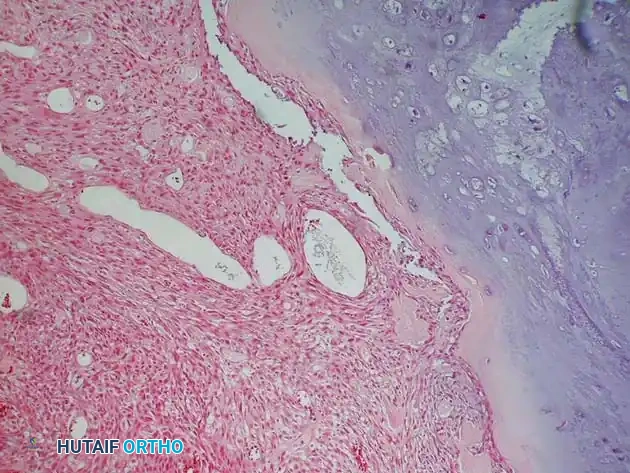

Fig. 22-9 A and B, Anteroposterior and lateral radiographs of the left fibula of a 7-year-old girl with Ewing sarcoma. Involvement of a large portion of the bone (or even the entire bone) is typical of Ewing sarcoma. C, MRI shows a large soft-tissue mass. D, Typical microscopic appearance of Ewing sarcoma.

Fig. 22-8 A, Anteroposterior view of the right proximal humerus of a 92-year-old woman with dedifferentiated chondrosarcoma shows an aggressive-appearing area (arrows) adjacent to an otherwise typical chondrosarcoma. B, Resected specimen shows these features. C, Typical microscopic appearance of dedifferentiated chondrosarcoma. High-grade spindle cell sarcoma is located adjacent to low-grade chondrosarcoma. D, Anteroposterior radiograph after reconstruction with an endoprosthesis.